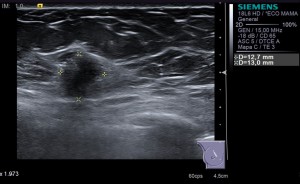

HALLAZGOS ECOGRÁFICOS